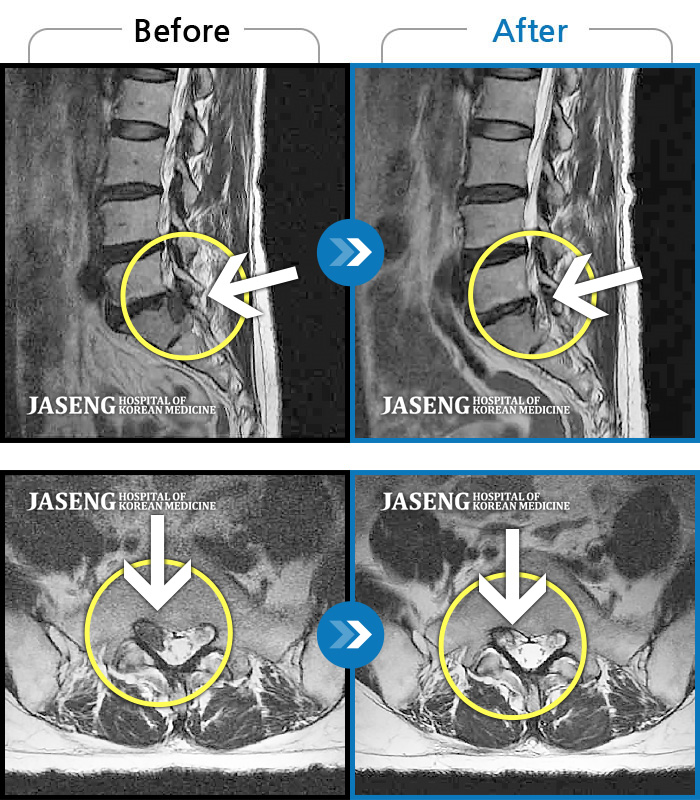

허리디스크

잠실 · 한상욱 원장

허리부터 왼쪽 엉치, 종아리 뒤 쪽까지 저리고 아파서 걸을 수가 없어 구급차타고 내원했다.

촬영시기

2021.01.08 ~ 2021.08.13

2021.09.10

조회수 1,981